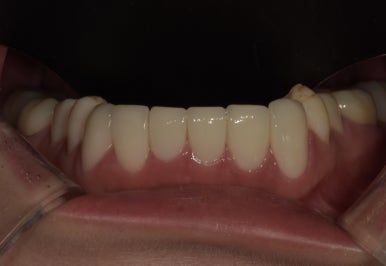

12전치 라미네이트, 크라운 치료 후

2023-07-05

1주일 후 최종적으로 보철물 제작이 완료되어 부착까지 진행해드렸는데요.

바뀐 모습 어떠신가요? 정말 몰라볼 정도로 확연하게 개선이 되었죠?

특히 오른쪽 아래 #42 치아는 기울어져 있던 치아가 반듯하게 개선되어 훨씬 고르게 변했고,

주변 치아와 조화가 잘 이루어지는 모습입니다.